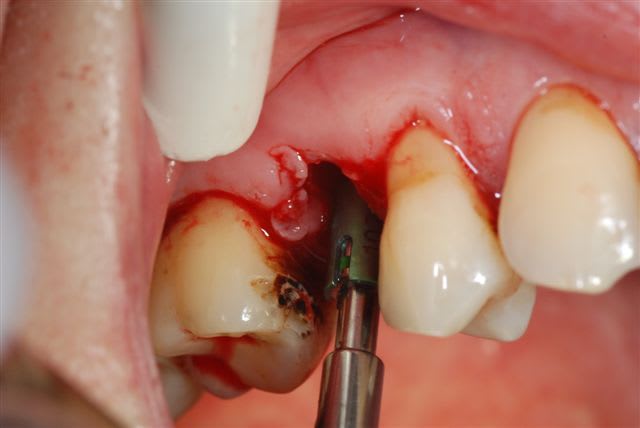

suite de la prémolaire fracturée: extraction , mise en place d'un implant tekka diametre 4 longueur 15 mm pour aller chercher un bon ancrage primaire. Il y avait 2 mm d'espaceentre l'implant et la corticale en vestibulaire et 1 mm en palatin, j'ai comblé au bio-oss et tracté la muqueuse sans tensions pour le recouvrir.

pas de photos du bio-oss en place car assistante absente et donc galère pour prendre la photo à ce stade.